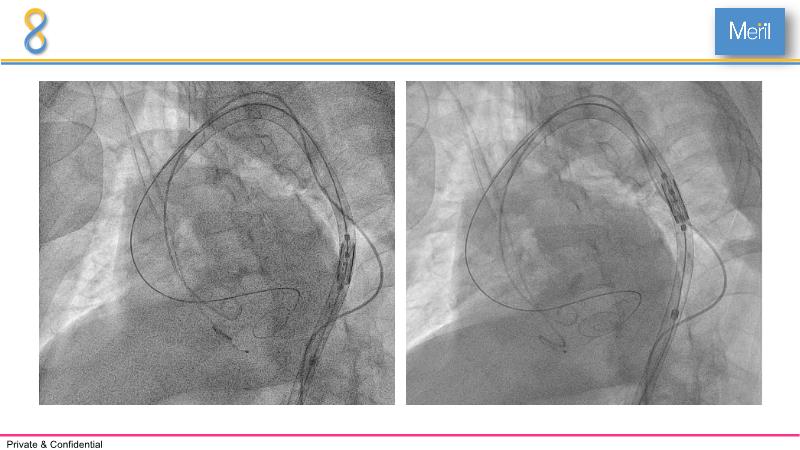

Through the presentation of several compelling cases, including an 88-year-old male with CKD, RBBB, moderate LV dysfunction, and severe aortic stenosis, a Type 1a bicuspid native AS, and an extraordinary TAVI in an 83-year-old with acute heart failure and comorbidities, this session will dive into the Myval Octapro THV. Learn about its key features, procedural impact, and potential clinical benefits. Discover the Octalign technique for predictable and precise commissural and coronary alignment, preserving coronary access. Gain insights into precise sizing, positioning, and deployment of the Myval THV series in real-world scenarios, and explore the relevance of pivotal Landmark RCTs in clinical practice.

- To learn about the novel Myval Octapro THV - Key features, the procedural impact and potential clinical benefits.

- To know the Octalign technique which enables predictable and precise commissural and coronary alignment thus preserving coronary access

- To understand the technique of precise sizing, positioning and deployment of Myval THV series in real world clinical scenarios